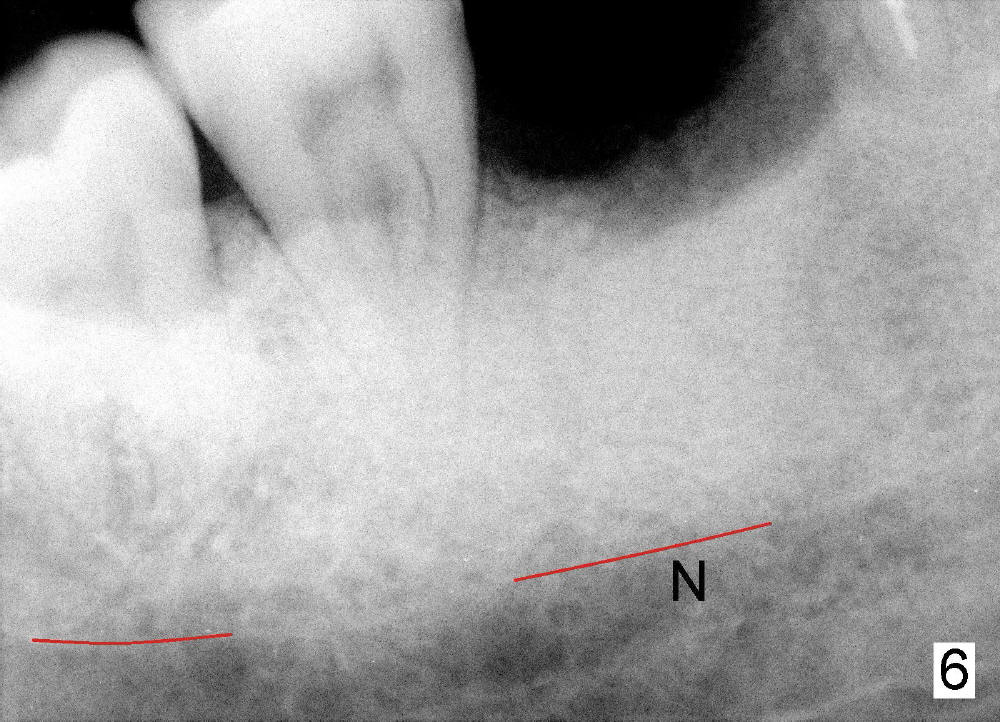

In contrast, the bite block of an endo X-ray device is vertical and narrow mesiodistally (Fig.4: B, as compared to Fig.1). It can be inserted into the edentulous space after extraction (Fig.5: B); the sensor (S) is placed deeply into the lingual vestibule. The corresponding PA does not show the coronal portions of crowns and roots next to the edentulous area (Fig.6), but it shows the the inferior alveolar nerve (N). It would be the best to measure the bone height and do treatment planning on the image as will be shown in Fig.10), since the endo device may not be inserted deep enough intraoperatively as shown below.